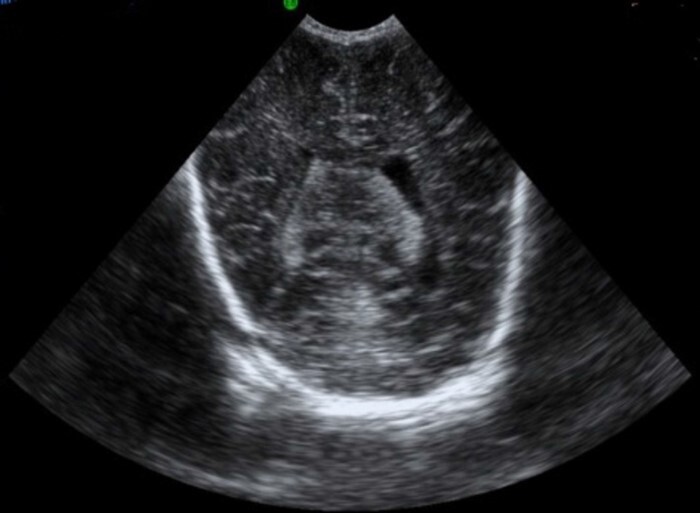

Neonatology Ventricle Asymmetry 2 Image